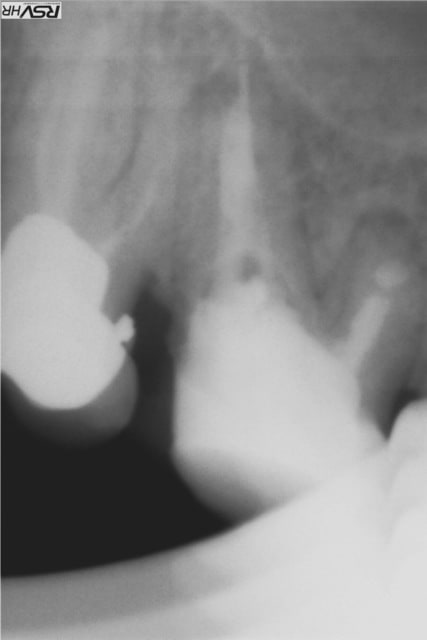

Les délires continuent !(clin d’œil doc Marcus)

37 fêlure-fracture au niveau du plancher en cours de RTE(1er radio avant RTE)

extraction dans la séance forage entre les racines extraction des racines re- forage après dans le septum

pose implant 7 mm long10mm le 11.06.2012

le 25.09.2012 pose d'un faux moignon titane transvissé et

couronne provisoire

RTE en cours sur 36

CCM définitives après

CBCT en 2014 OK pour l'implant